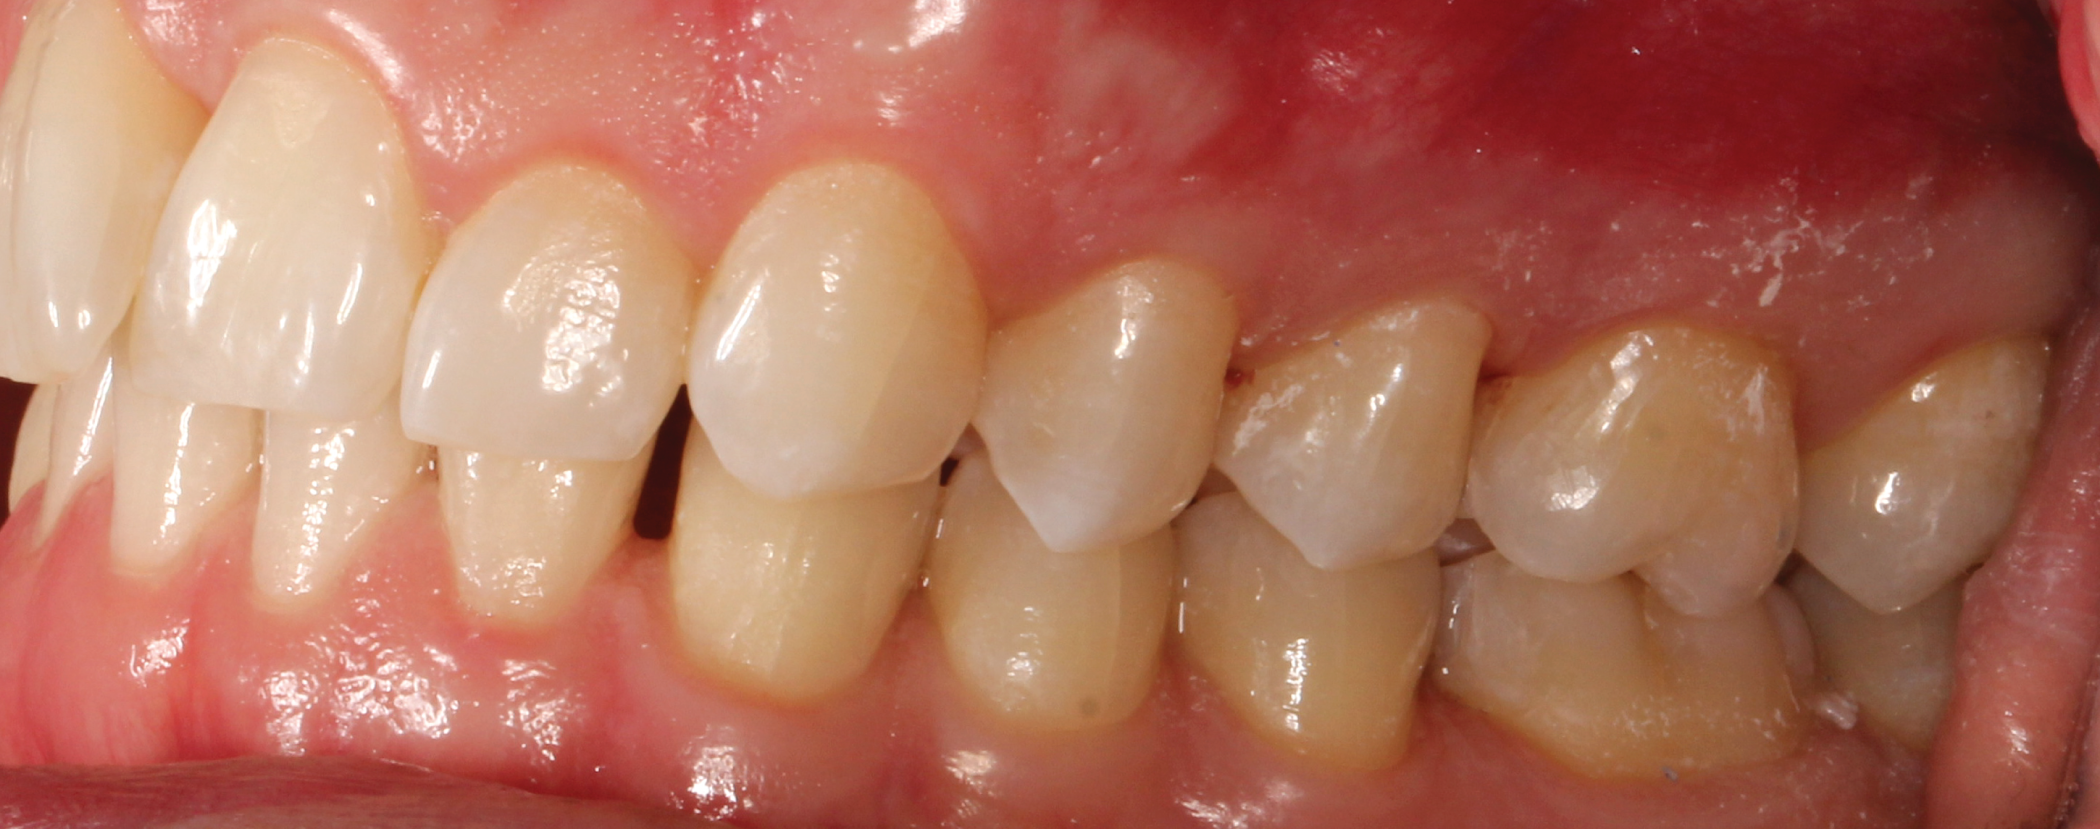

Fig. 7: Pre-op (right lateral view) Fig. 8: Pre-op (left lateral view)